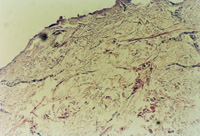

3-23 对其“皮点”进行组织学检查,该组织为从皮下组织中再生出的微血管、胶原组织、表皮细胞组织组成的再生皮肤组织团

3-24 该“皮点”逐渐扩展为皮肤组织团,各皮肤组织团互相融合